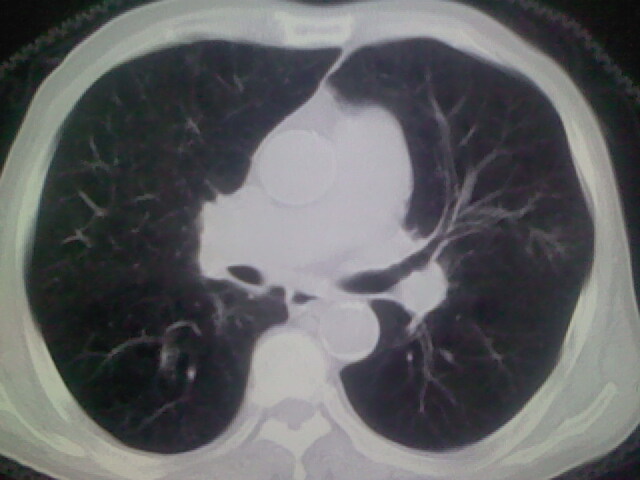

男,70y,胃占位,重度贫血,黑便3月余,伴恶心,纳差,乏力

1)考虑右肺上叶周围型肺癌并纵隔及右颈部淋巴结转移,肝脏多发性转移。2)肺气肿。3)冠状动脉及主动脉钙化。

1)考虑右肺上叶周围型肺癌并纵隔及右颈部淋巴结转移,肝脏多发性转移。2)肺气肿。3)冠状动脉及主动脉钙化。胃未充盈而且影像不太清楚,不好确定

资料不清晰啊,肺内病灶内可见多发钙化影,结核不能除外.肝内符合转移瘤表现.既然楼主提供胃内占位,那原发灶还是考虑来源于胃腔.